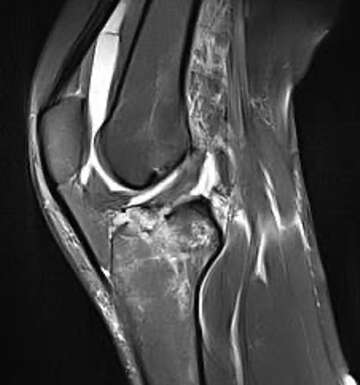

Imaging of the knee joint

The knee is one of the most commonly injured joints in the human body, especially in the setting of sports injuries. Sudden twisting movements that place torsional stress on the joint with the foot in a fixed position often...read more